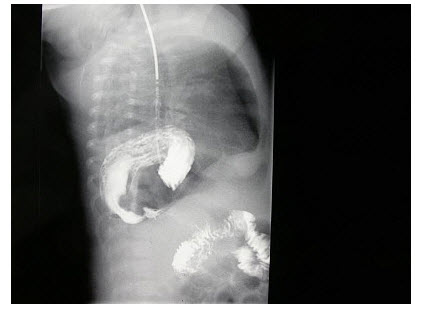

179、单项选择题

女,1岁10个月,右肘部外伤,如图所示,最佳的诊断为()

A.全骺分离

B.肱骨髁上骨折

C.肱骨髁上骨折并肘关节脱位

D.内上髁骨骺损伤

E.内上髁骨骺损伤并肘关节脱位